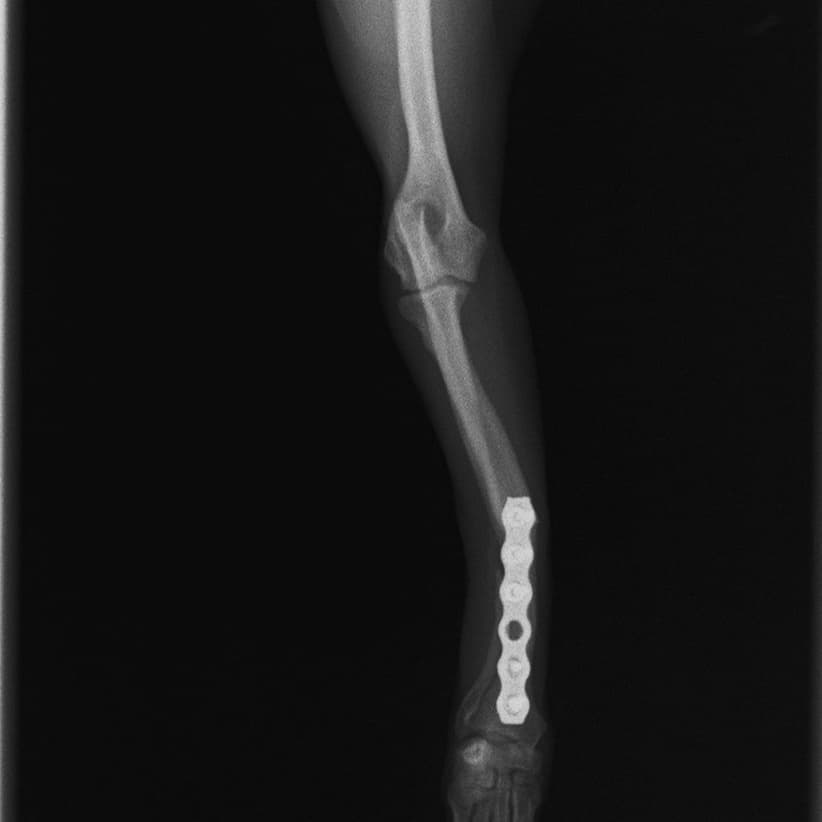

橈尺骨骨折 : 症例1 | 症例2 | 症例3 | 症例4 | 症例5 | 症例6 | 症例7

: 症例8 | 症例9 | 症例10 | 症例11 | 症例12 | 症例13 | 症例14

: 症例15 | 症例16 | 症例17 | 症例18 | 症例19 | 症例20 | 症例21

Advanced Locking plate system と Locking compression plate system

当院ではAdvanced Locking plate system(ALPS)と、Locking compression plate system(LCPS)という骨接合法で骨折症例の治療を行っています。

トイプードル 右遠位橈尺骨短斜骨折のALPSによる内固定

LCPは、スクリュー(ネジ)とプレート(金属の板)をロックする特殊な構造により骨折部位を固定する新しい世代のプレートシステムです。ひとつのホールでロッキングスクリューとスタンダードスクリューの使用を選択できるユニークな構造をしているため、骨折断端間の圧迫を目的とした従来型プレート固定法に加え、高い角度安定性を有するロッキングスクリューを用いた固定法の選択が可能です。従来のプレートシステムでは困難だった部分の骨折や癒合不全の症例に高い治療効果をもたらします。